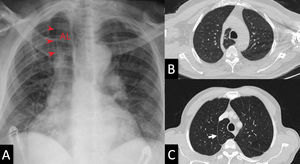

Most cases of azygos lobe are incidentally discovered but there are cases of tumors, pneumothorax, and consolidations found in the azygos lobe.1,3,4 A displaced azygos vein can often be confused with a pulmonary nodule and a consolidated azygos lobe can be confused with a pulmonary mass.1-4 An understanding of the azygos lobe anatomy is important for all clinicians especially pulmonologists, radiologists, and thoracic surgeons (Fig. 1).

Chest frontal view radiograph (A) demonstrating the hyperdense lateral borders (arrowheads) of the azygos lobe (AL). Radiographs were taken with a 32kW Mobile X-ray unit (70 kVp, 320 mA, 0.5 sec). Superior (B) and inferior (C) axial CT images identifying the azygos vein (B) which separate the azygos lobe from the superior lobe. CT imaging was high resolution CT (HRCT) (slice thickness: 1 mm, scan time: 1 sec, 120 kV, 100 mA). The white arrow (C) shows the boundary of the lobe which is separated by 2 layers of visceral and pleura.